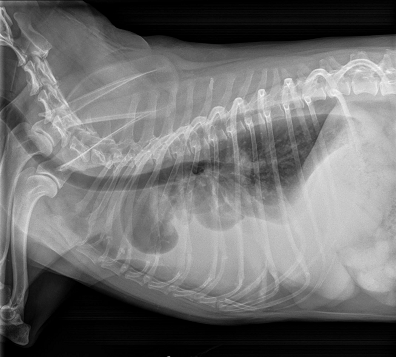

Radiography (x-ray) is used to determine if the heart is enlarged

(particularly the left atrium and left ventricle), if the veins from the

lungs to the heart are distended, or if fluid is beginning to develop in the

lungs.* X-rays also will show any enlargement of

the pulmonary vein, a classic symptom of congestive heart failure (CHF).

• VHS measurements to detect enlargement

Cardiologists use x-rays to evaluate the size and shape of the heart in

order to assess the severity of MVD.

The Vertebral Heart

Size or Scale or Sum (VHS) is an objective means of measuring

heart size.

As

the x-ray image above shows, using calipers, they

measure the length (from the apex to the bottom of the left mainstem) and width

(at

its widest point perpendicular to the lemgth measurement) of the heart

on a lateral x-ray and compare those dimensions

to the number of veterbrae from T4 to T12, to calculate the VHS value. Since

the dog's own vertebrae are used for comparison, each VHS value is

normalized to the dog's overall body size.

The VHS is not intended to diagnose CHF. It's purpose is to enable veterinarians to more accurately determine enlargement of the heart (called cardiomegaly or dilation) and the progression at which the enlargement is occurring, which usually is due to MVD. However, since MVD normally initially causes only the left atrium (LA) to enlarge, the VHS method is not precise enough to measure only the size of the LA. See for example, the x-ray at left, which shows that the VHS measurements entirely miss the bulbous enlarged LA in the upper right corner of the heart. (Image from Hezzell, 2018.)